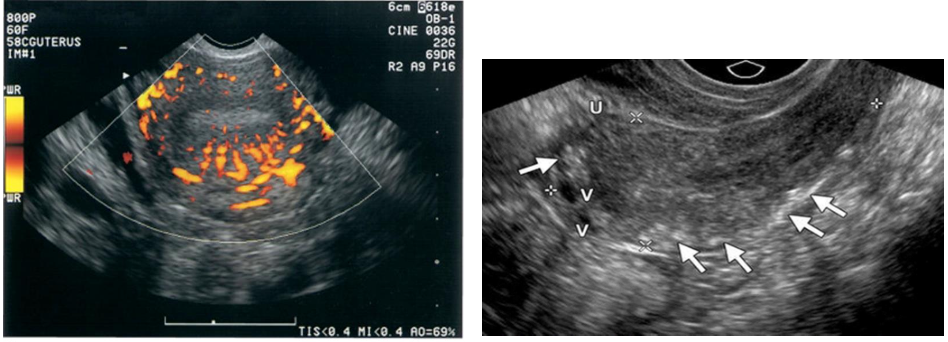

Doppler studies have also proven helpful in differentiating uterine pathology, as color flow studies of

uterine masses show that myomas and sarcomas typically demonstrate a feeding artery, but

adenomyosis rarely demonstrates feeding arteries.

Adenomyosis

-consist of vascular plexus of arteries and veins

without intervening capillary network.

Rare; usually involving myometrium and rarely endometrium

Congenital or teratogenic (acquired) due to pelvic trauma, surgery, or gestational

trophoblastic neoplasia

Clinically, women of childbearing years have metrorrhagia with blood loss and anemia.

Diagnosis critical because dilation and curettage may lead to catastrophic hemorrhaging

Sonographic findings

Sonographically, serpiginous, anechoic structures seen within the pelvis

Uterine AVMs may appear as subtle myometrial inhomogeneity, tubular spaces within myometrium,

intramural uterine mass, endometrial or cervical mass

Color Doppler diagnostic to show blood flow within anechoic structures

May be florid-colored mosaic pattern with apparent flow reversals and

areas of color aliasing

Spectral Doppler shows high-velocity, low-resistance arterial flow

coupled with high-velocity venous flow with arterial component.

Arteriovenous Malformations